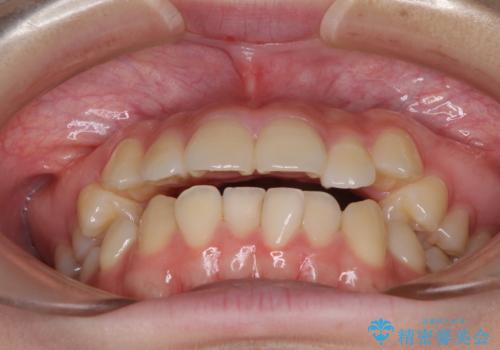

カリエール・ディスタライザーとインビザラインを用いた八重歯の改善

- 前歯の叢生と上顎左右の八重歯を気にして来院された患者様です。

奥歯の咬み合わせを見ると、左側は上顎が下顎に対して相対的に前方にあり、上下の前歯が接触していない状態でした。

咬み合わせを改善するためには、左側上顎臼歯を後方に移動させた咬み合わせにする必要があります。

インビザライン単体で改善することも可能性もありますが、インビザライン単体で達成する可能性が低いと考えられたため、カリエール・ディスタライザーという補助装置を併用して、より確実性を上げることとしました。

奥歯の咬み合わせを改善しながら、並行してインビザラインで歯列を整えることとしました。

カリエールディスタライザーを併用したことで、左側臼歯の咬み合わせを確実に改善させることができました。